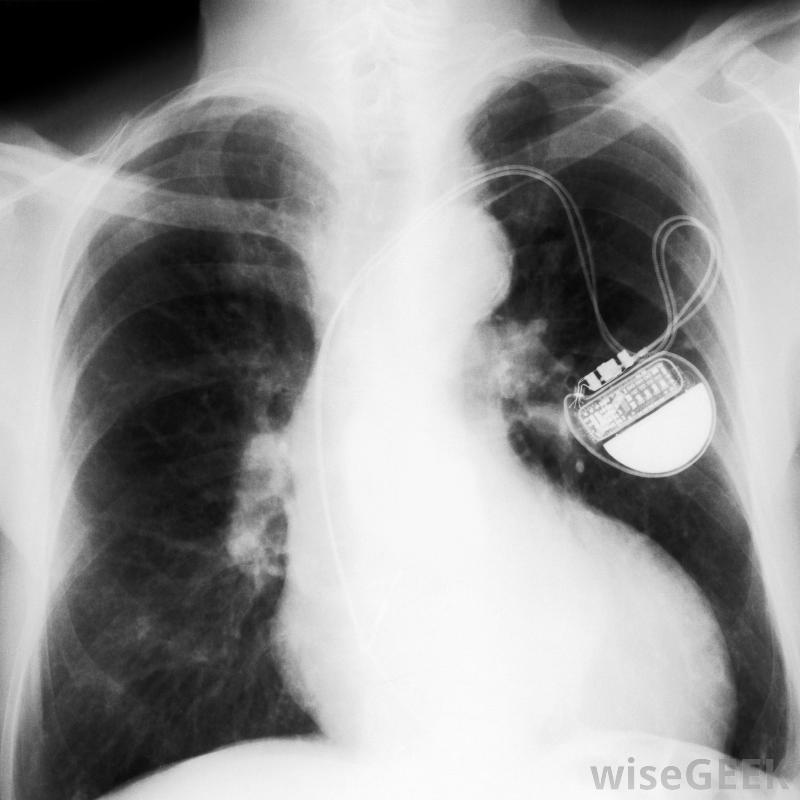

起搏器导线,也叫导线,是一根细线,一端与设备的发电机相连,另一端与心脏相连。每个起搏器可能有两条或两条以上的导线连接到右心房和右心室,有时还连接到左心室。导线的一端有一个电极,电极与心脏相连,以获取心脏的自然电脉冲并将这些信息发送回发生器。

起搏器永久性地监测心房和心室的心脏节律。起搏器导线有几种形式,虽然大多数是由金属制成的,并具有某种绝缘涂层。有些采用螺旋式设计,而另一些则在一端有小尖头连接到机身上。电线可以是直的、窄的,或者是"J"形或类似形状,以便更有效地融入中庭许多起搏器使用一组导线来连接心脏的各个区域。具有旋入机制的导线在植入后能够很快保持原位。然而,那些带有尖齿的起搏器,通常更准确地定位心脏不规则。带有螺丝装置的导线更常见,但医生将最终判断每个患者需要哪种类型的起搏器导线。在放置过程中,起搏器导线插入胸部左上角的静脉,与放置起搏器的位置相同。医生通常使用透视镜(一种X光片)来观察导线穿过静脉并进入心脏的正确位置。这通常被认为是一种小手术,而且病人一般不需要全身麻醉。手术通常在诊所或医生办公室进行。起搏器导线发生故障的情况非常罕见,因为它们的设计相对简单。更常见的是起搏器口袋可能会发生感染,而且整个系统都会被更换。很少有特定型号的起搏器或导线会因为设计或功能错误而被召回。偶尔需要向医生咨询以确保设备正常工作。当电池电量不足时,每五到十年更换一次起搏器。